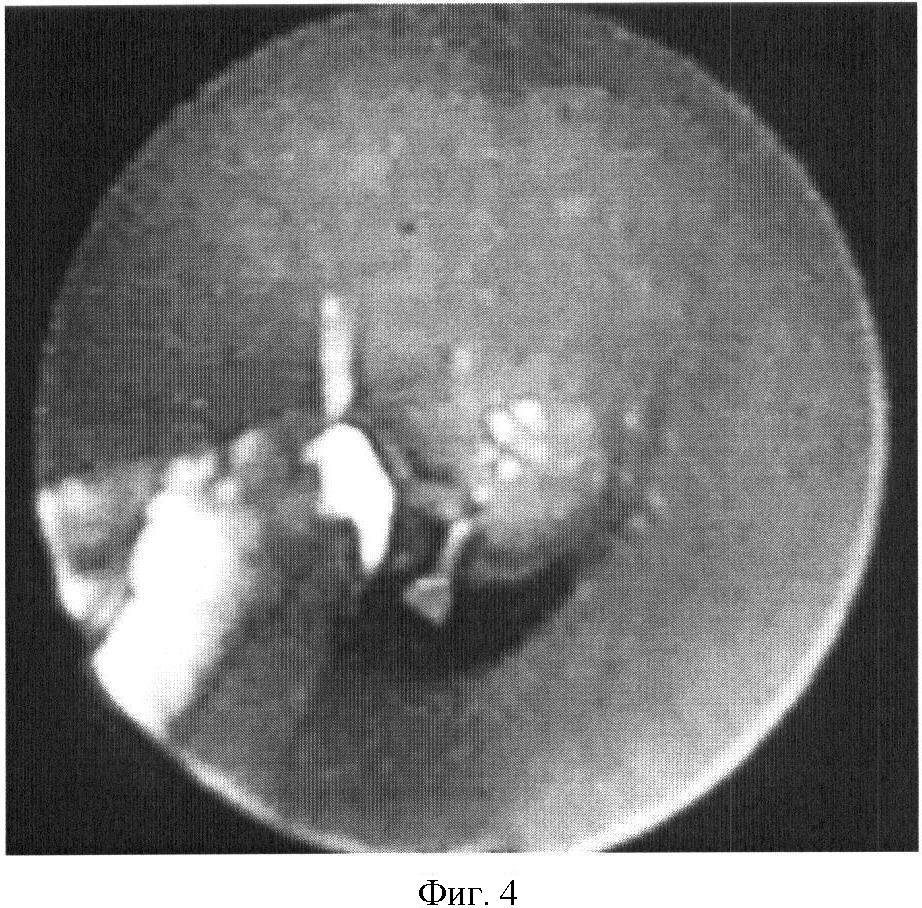

На фиг.1 представлена рентгенограмма пищевода с контрастным веществом: определяется контрастирование трахеопищеводного свища. На фиг.2 представлена эндоскопическая картина просвета пищевода: устье трахеопищеводного свища указано стрелкой. На фиг.3 представлена эндоскопическая картина просвета пищевода: предварительно в устье трахеопищеводного свища, открывающегося в просвете трахеи, было ведено 0,8 мл красящего вещества (метиленовой сини), после этого в просвете пищевода определяется прокрашивание устья трахеопищеводного свища (указано стрелкой). На фиг.4 – пломбирование устья трахеопищеводного свища тахокомбом, предварительно устье свища было последовательно подвергнуто электрокоагуляции и химиокоагуляции (96% этиловый спирт). На фиг.5 – клиппирование запломбированного устья свища. На фиг.6 – контрольная эзофагоскопия, выполненная через 3 месяца после операции: в просвете пищевода в области устья трахеопищеводного свища определяются две скрепки. На фиг.7 – контрольная рентгенограмма после эндоскопического лечения (через 3 месяца): в области трахеопищеводного свища определяется незначительный дефект наполнения (указан стрелкой), трахеопищеводный свищ не контрастируется.